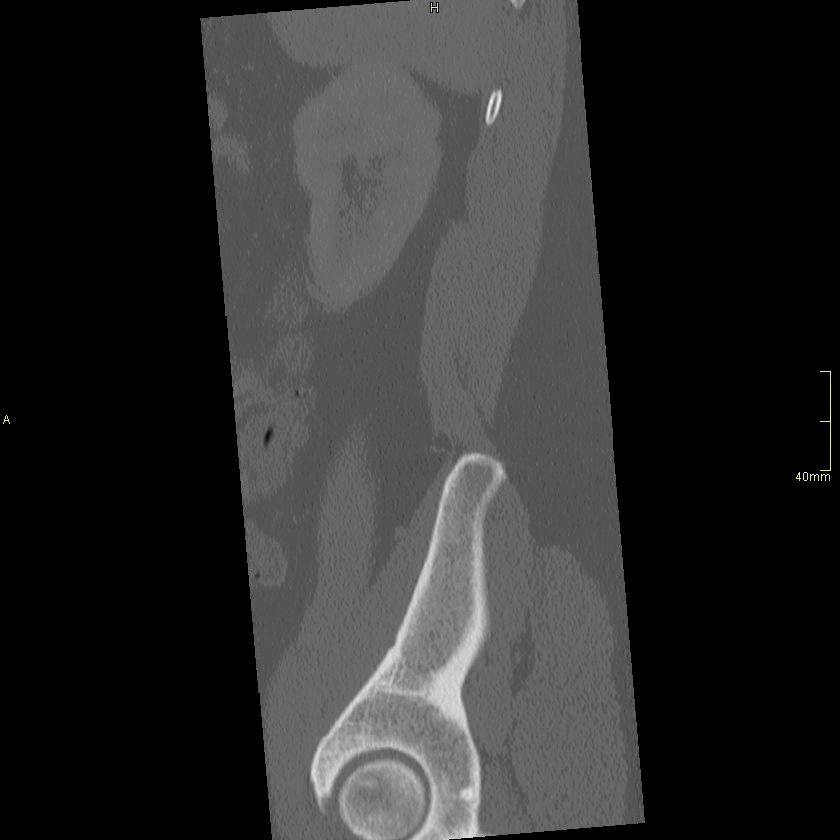

CT Lumbosacral Spine Contrast- Bone window (sagittal)